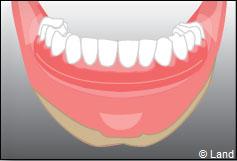

Les implants peuvent aussi servir à stabiliser un appareil amovible au maxillaire supérieur comme au maxillaire inférieur. Dans ce cas, les implants retiennent la prothèse amovible par des systèmes d’attachement.

Deux techniques sont possibles. Elles font appel à la barre de rétention ou aux boutons-pressions.

Exemple d’une réhabilitation complète implantaire

Situation clinique initiale